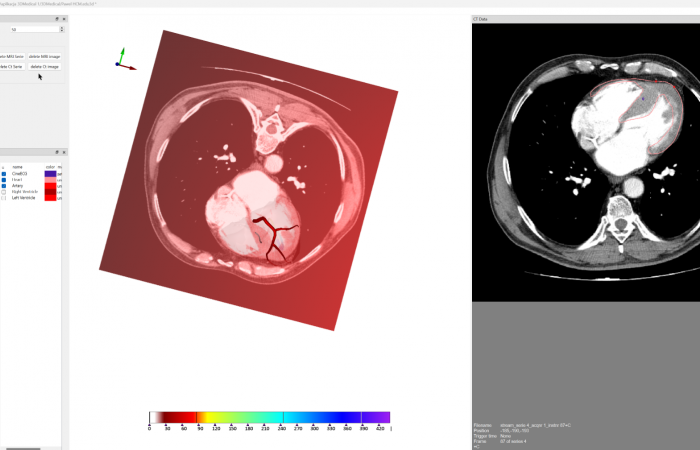

Pracownia Funkcjonalnego i Wirtualnego Medycznego Obrazowania 3D (Pracownia 3D-FM) funkcjonuje w strukturze Zakładu Diagnostyki Obrazowej Szpitala Uniwersyteckiego w Krakowie pod kierownictwem Prof. dr hab. Tadeusza Popieli. Jej celem jest opracowanie i wdrożenie innowacyjnych metod przetwarzania oraz analizy sygnałów i obrazów medycznych, w tym wykorzystanie technologii rzeczywistości wirtualnej oraz metod obrazowania funkcjonalnego. Rozwiązania te wspierają przedoperacyjne planowanie, monitorowanie procedur medycznych oraz wzbogacają proces diagnostyczny o nowe formy wizualizacji danych medycznych.

Pracownia 3D-FM zajmuje się m.in. następującymi obszarami:

- Tworzeniem modeli 3D do celów przedoperacyjnego planowania oraz wizualizacji diagnostycznej.

- Obrazowanie Medyczne 3D

- Segmentacja i analiza danych DICOM

- Rekonstrukcja danych medycznych

- Obrazowanie funkcjonalne

- Modelowanie fizjologiczne